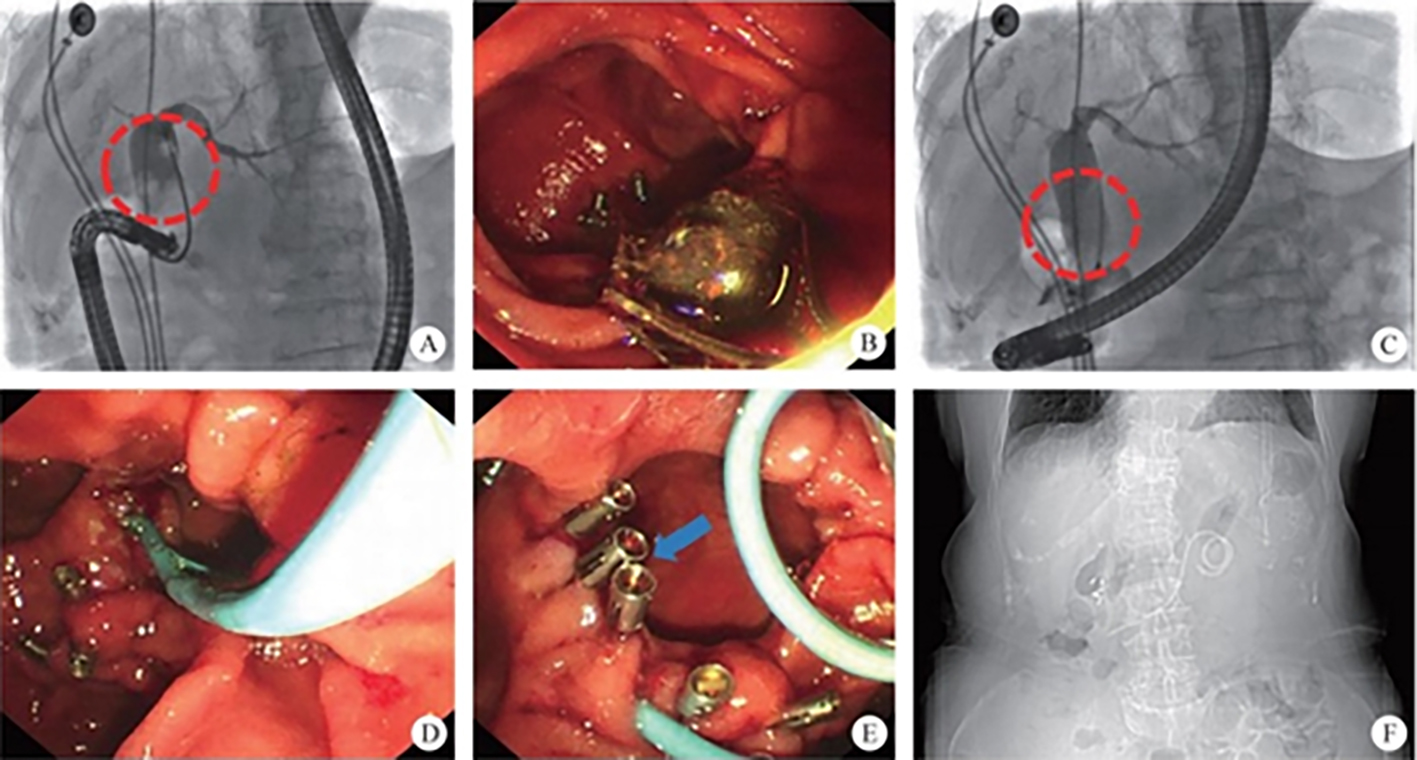

(2) Development of pancreaticobiliary endoscopy: endoscopic retrograde cholangiao-pancreatography (ERCP) has developed steadily for more than half a century, and finally blazed the visible field of the pancreaticobiliary diseases after the emergence of biliary and pancreatic vision equipment, which explored the diagnosis and treatment scope of the endoscope, making precision diagnosis and treatment become a reality. On that basis, a series of SMIS surgeries for biliopancreatic diseases have obtained decisive progress, including laser lithotripsy under direct choledochoscope with preserved sphincter, exploratory pancreatic duct with cholangiopancreatic vision system, super minimally invasive photodynamic therapy under the pancreatic duct, radiofrequency ablation of the bile duct under direct choledochoscope, direct choledochoscopy with a papillary support for cholecystolithiasis and extraction of biliary calculus, etc.

The normal common bile duct pressure is 10–15 mmHg (1 mmHg = 0.133 kPa) higher than that of the duodenum, but the basal pressure of the sphincter of Oddi is about 4 mmHg higher than that of the pancreatic biliary system, so that the sphincter of Oddi can effectively prevent the regurgitation of duodenal contents and avoid gastrointestinal bacterial retrograde infection. EST is usually performed before duodenal papillary intubation, which damages the integrity of the sphincter of Oddi, leading to sphincter relaxation and a loss of the anti-reflux physiological function. In 2020, a study was conducted to investigate the feasibility and effectiveness of duodenoplasty to restore the function of the sphincter of Oddi. The study prospectively included 30 patients who had undergone EST lithotomy and duodenal papilloplasty; 80% of patients had a basal pressure of the sphincter of Oddi after duodenal papilloplasty >10 mmHg, and the pressure parameter was resumed after the operation, and was unrelated to the healing process. Postoperative mild pancreatitis occurred in six cases, and a recurrence of the stone in one case. Studies have shown that duodenal papilloplasty can restore the basal pressure of the sphincter of Oddi, thus restoring its anti-reflux function and possibly preventing the reappearence of gallstones and cholangitis.

The intrahepatic bile duct is the relative blind area of SpyGlass. The treatment of intrahepatic bile ducts by retrograde transpancreatobiliary endoscopy can avoid the trauma of surgical choledochoscopy and sinus infection caused by percutaneous choledochoscopy. However, there are still few reports on the diagnosis and treatment of intrahepatic bile ducts by choledochoscopy in China and abroad, and they only concern grade-I and II intrahepatic bile ducts, even if currently the surgical choledochoscopic fiber can enter directly intrahepatic bile ducts above grade IV. In 2021, a study evaluated the effect of SpyGlass on grade-I and II intrahepatic bile duct lithotomy, whereas laser lithotripsis is performed for large or impacted gallstones at the same time. The results showed that the diagnostic rate of SpyGlass was 97.14%, the success rate of one-time lithotomy was 85.71%, the occurrence rate of complication was 8.57%, the postoperative residual stone rate was 14.28%, showing that SpyGlass can effectively diagnose and treat intrahepatic bile duct stones. But so far a multi-center study is still lacking to support its clinical promotion and application. In addition, SpyGlass can also be used to remove gallstones through the gallbladder duct while preserving it, with a high rate of stone removal, while being less traumatic, with rapid recovery and effective resumption of gallbladder function.

Gastrointestinal endoscopic super minimally invasive surgery (eSMIS) is a branch of SMIS operations. After multiple years of development and clinical practice, presently eSMIS has a perfect endoscopic technique, a nomenclature of procedures and implementation principles, as well as specific development perspectives. Over the recent 10 years, endoscopic scholars in China have been constantly innovating and developing a series of SMIS surgical methods according to four directions, namely, natural, tunnel, puncture, and multi-cavity channels. For example, in the SMIS operation of early gastric cancer, full-thickness resection of the lesion by natural channel, full-thickness resection by multiple-cavity + lymphadenectomy approaches, the technique of sealing large wounds after non-full-thickness resection, and the traction technique in non-full-thickness resection; in the treatment of large-area early esophageal cancer by tunnel channel, autologous skin graft was used to prevent esophageal stenosis after large esophageal defect, and for the diagnosis and treatment through the muscularis propria to the outside of the digestive lumen; some breakthroughs in SMIS operations of the bile pancreatic disease, including laser lithotripsy under direct choledochoscope with sphincter preserved, exploratory pancreatic duct with cholangiopancreatic vision system, super minimally invasive photodynamic therapy under pancreatoscope, radiofrequency ablation of bile duct under direct choledochoscope, direct choledochoscopy with a duodenal papillary support for the extraction of gallbladder silt stones and of biliary calculus, etc., have been achieved.